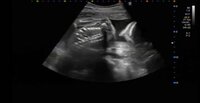

その後に更新したブログでは、妊婦健診の際に「先生はいつもと違うから体重のことは特に言われなかった」と明かす一方で「逆子でした」と報告。「がーーーーーーーーん」とショックを受けた様子でつづり「やはり冷やしたのが良くなかったのでしょう・・・。今日から逆子体操だ」とコメントした。

また「やっぱりもう今日は気力がない」と述べ「寄り道したかったけど 眠いし吐きそうだし暑いし今日は帰ろう」と説明。「逆子の赤子よ。母ちゃんのことを許してくれ。ご機嫌なおしてでんぐり返ししておくれ」と胎児に呼びかけ、「そんで顔わたしに似てた。ごめーん」と報告し、ブログを締めくくった。